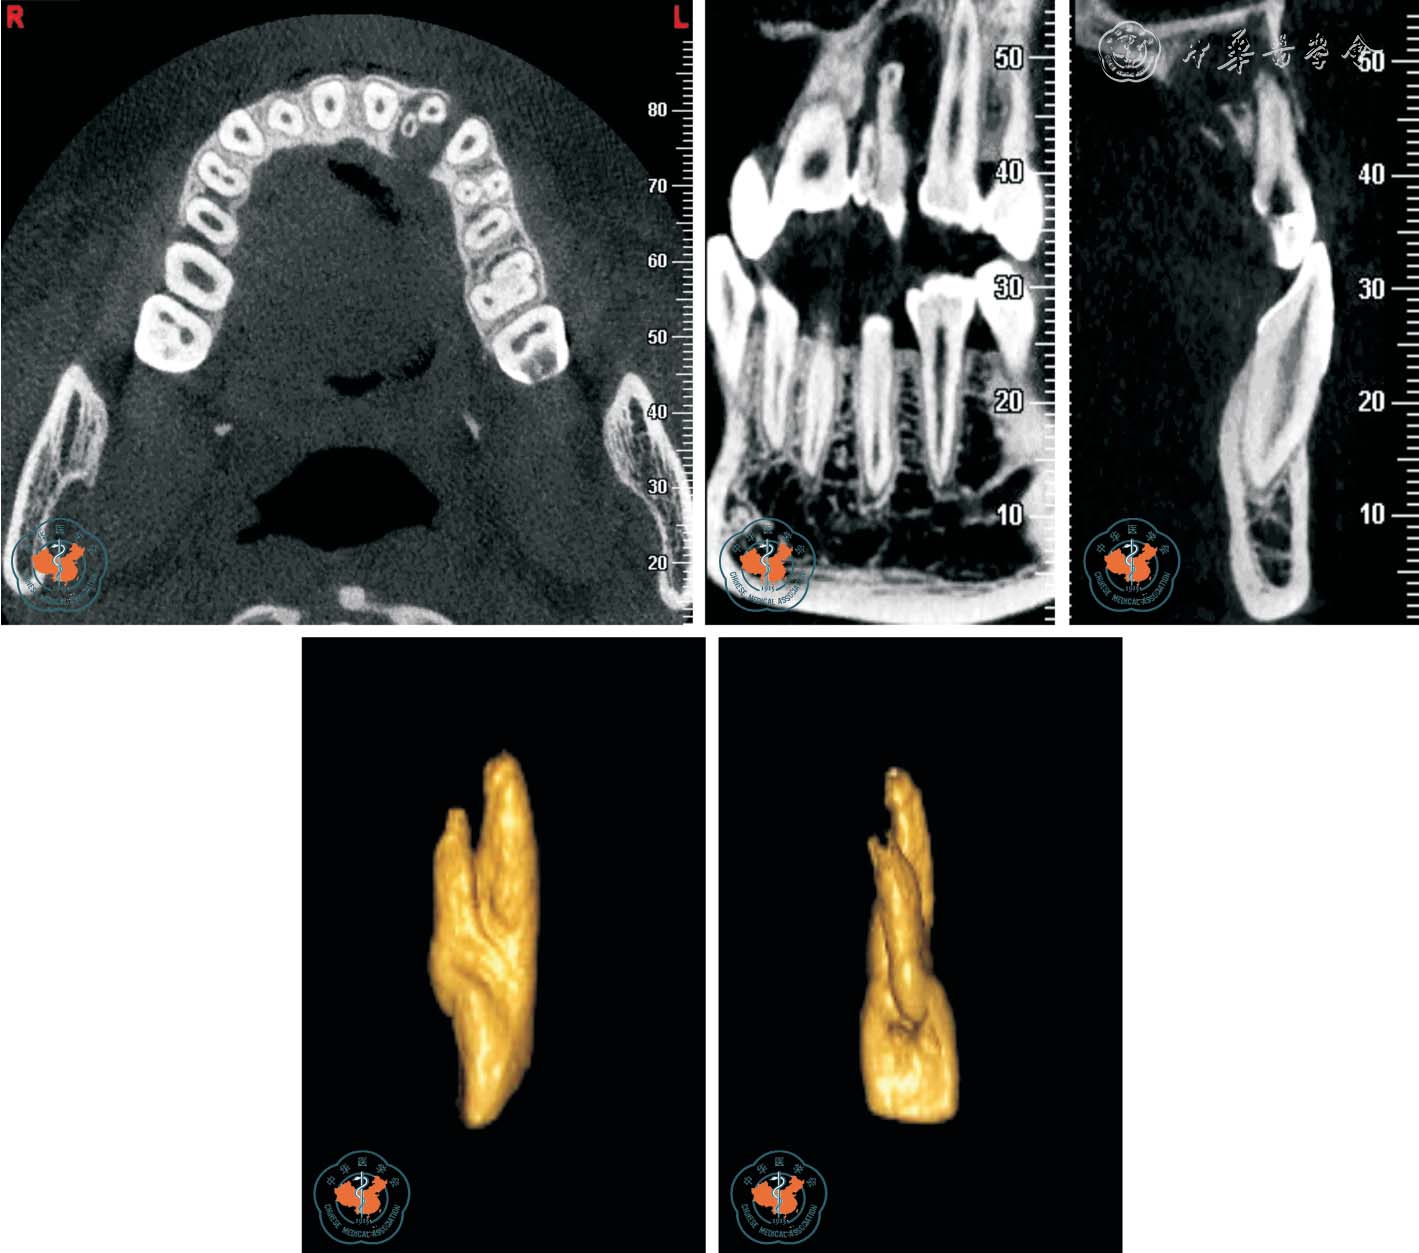

3. 对根管治疗术质量的评价:CBCT 图像可了解牙髓组织的解剖结构,特别是在复杂根管治疗前及术中,可以随时调用近远中向、冠根向、颊舌向的解剖图像,从不同的方向及断层进行切片分析,能够清晰地了解根管的形态,帮助根管治疗,使治疗更彻底,根管治疗后还可以用来监测根管治疗效果,减少了漏诊(图5)。

图5 CBCT 轴位、CPR 及MPR 重建冠、矢状位图像清晰显示上颌第一、二磨牙(牛牙症)